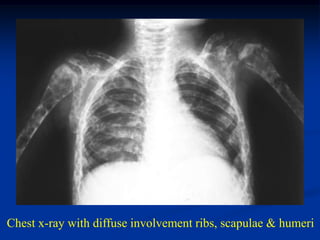

CLASSIC         Case #447

3 year female with LS disease skull

Chest x-ray with diffuse involvement ribs, scapulae & humeri

Diffuse involvement pelvis and hips

Bilateral humeral involvement